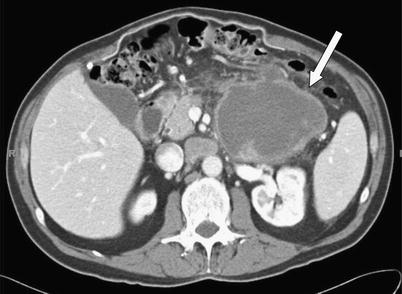

Fig. 7 A 65-year-old male with acinar cell carcinoma of the pancreatic uncinate process. Axial CT image (A) demonstrates a subtle hypodense mass (arrow) exophytically extending inferiorly from the pancreatic head/uncinate process. Coronal CT image (B) demonstrates enhancing tumor thrombus (arrows) extending throughout the main portal vein and SMV.